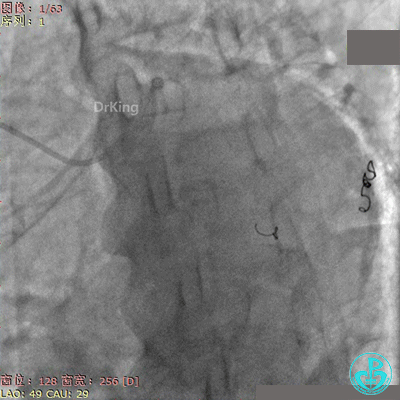

再次上台造影,钝缘支分支远端弹簧圈封堵处仍然有造影剂外漏。

明胶在血管怎么降解并发症丨前降支CTO同侧逆向开通时侧支血管破裂,弹簧圈联合明胶海绵封堵_https://www.jmylbn.com_新闻资讯_第48张

明胶在血管怎么降解并发症丨前降支CTO同侧逆向开通时侧支血管破裂,弹簧圈联合明胶海绵封堵_https://www.jmylbn.com_新闻资讯_第49张

心包穿刺引流。

2根导丝进入到钝缘支分支远端,1根导丝送入微导管,另外1根导丝送入2.5×15mm球囊,2.5×15mm球囊远端Marker与微导管齐口(自制OTW球囊),经微导管缓慢推注明胶海绵糊。

明胶在血管怎么降解并发症丨前降支CTO同侧逆向开通时侧支血管破裂,弹簧圈联合明胶海绵封堵_https://www.jmylbn.com_新闻资讯_第51张